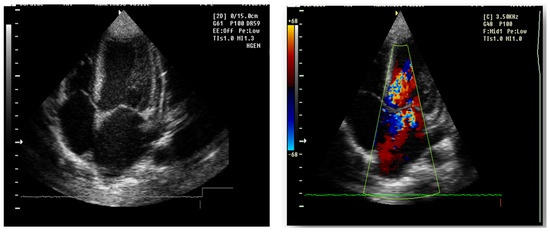

Figure 9. Echocardiography 4 chamber transthoracic apical view: echodense mitral and aortic valve, II-degree mitral regurgitation and I degree aortic regurgitation, pulmonary and tricuspid valve echodense, with I degree regurgitation. Left atrium and Left ventricle dilatation, normal kinetics, EF 70%, inferior vena cave not dilated, with inspiratory collapse, E/A > 2.

Echocardiography (Figure 9)

mitral insufficiency second degree

aortic insufficiency first degree

tricuspid insufficiency first degree

dilatation of the left heart

ejection fraction 50%

fine pericardial reaction, 3 mm

Forty-six days after admission, the patient suddenly complained one morning of epigastric pains, nausea and palmo-plantar burning, associated with a hypertensive episode (BP 180/110 mmHg), for which reason a hemodialysis session was performed urgently, extracurricular. In the same evening, at a BP value of 160/100 mmHg, at rest, the patient presented a sudden and severe worsening of the general condition, dyspnea with orthopnea, intense wheezing, SaO2 89–91%, tachycardia 140/min, subcrepitants disseminated on both lung areas. The suspicion of cardiogenic acute pulmonary edema was confirmed by imaging (chest X-ray—Figure 7, Table 1). Electrocardiographic evaluation (Figure 8, Table 1) revealed subendocardial myocardial ischemia, and echocardiography revealed acute dilation of the left heart, as well as a fine pericardial reaction, 3 mm, without signs of cardiac tamponade (Figure 9, Table 1). At that moment, we made 2-h ultrafiltration, during which the signs of acute pulmonary edema subsided. After 60 min an increase in blood pressure up to 160/120 mmHg is noted, with the maintenance of negative T waves on the monitor. Hemodialysis was stopped and iv Nicardipin was administered, with good results.

The major sign of cardiac involvement in Fabry disease is left ventricular hypertrophy, but conduction disturbances such as short PR interval (due to accelerated conduction in the absence of the accessory pathway) and rhythm disturbances such as sinus bradycardia have also been reported. Cardiac ultrasound and ECG are indicated at baseline and at all follow-up visits. Holter testing is recommended only if indicated by symptoms, as severe arrhythmias are not usually encountered in early childhood [18]. In our case, the boy presented dilatation of the left cavities with secondary mitral and aortic regurgitation from the beginning. This could not be attributed only to hypertension secondary to chronic kidney disease, because it regressed after the initiation of enzyme replacement therapy. During the follow-up, he did not present any rhythm or conduction disorders, but the phenomena of myocardial ischemia were observed in the context of hemodialysis, requiring a change in the method of renal replacement.